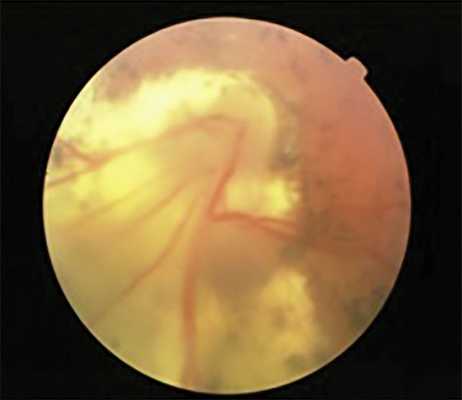

Кроме того, при самопроизвольном регрессе на 12 глазах с I—III степенью рубцовой РН в отдаленном периоде наблюдения сохранялись остаточные аваскулярные зоны на периферии сетчатки, а также анастомозы и сосудистые «щетки» на границе с аваскулярной сетчаткой, что косвенно подтверждает «незрелость» сетчатки на момент рождения. При этом, несмотря на локализацию патологического процесса в активной фазе РН в I или II зоне глазного дна, остаточные аваскулярные зоны определялись только на височной периферии, что свидетельствует о возможности продолженного васкулогенеза сетчатки уже после завершения активной фазы РН (рис. 3).

Рис. 3. Остаточные аваскулярные зоны и сосудистые анастомозы у ребенка 10 лет на глазу с рубцовой РН.